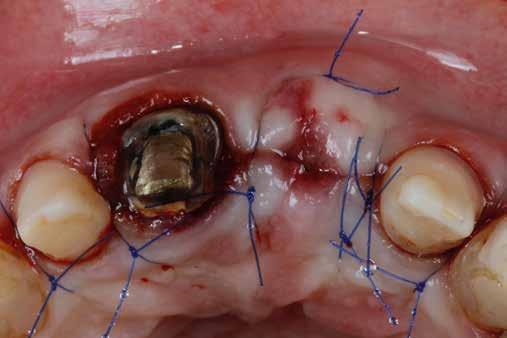

4. ábra: A fogszerkezet helyreállítása és a fogrestaurációs komplexum ellenálló képességének javítása érdekében ortodontikus extrúziót végeztek a szomszédos fogakra ragasztott drót és egy egyszerű rugalmas ligatúra segítségével.

5. ábra: Az extrudálás nyomon követése néhány hét múlva. Az extrúzió végén a lágyrészek kisebb mértékű újrakontúrozása történt. A szerző általában fibrectomia nélkül végzi az extrúziót, és az extrúzió végén a lágyrészek újrakontúrozását végzi.

6. ábra: A fog az extrúzió és a függőleges preparálás után. A függőleges preparáció a legjobb preparátum a fog szerkezetének megőrzése szempontjából, különösen akkor, ha minimálisan invazív megközelítéssel alkalmazzák. A szerző egy módosított vertikális technikát alkalmaz, amely nagyobb hangsúlyt fektet a pericervikális dentin fenntartására.

7. ábra: A bukkális szerkezet összehasonlítása extrudálás előtt/után . A maradék fogazati struktúra okklusális terhelése most sokkal kedvezőbb a hosszú távú eredmény szempontjából .

8. ábra: Ideiglenes eltávolítás. 9. ábra: Még a szájpadlásfalon is volt fogazati struktúra-gyarapodás. A szájpadlásfal mintegy 35%-a már szilárd fogazati struktúrán van. Ez a jobb biomechanika miatt sokkal jobb eredményt tesz lehetővé a későbbi restauráció számára.

10. ábra: A cirkónium-dioxid korona cementálása üveg-ionomer cementtel . Ezzel a megközelítéssel nyilvánvaló, hogy a ferrule menynyisége a szomszédos fogakra gyakorolt bármilyen komplikáció nélkül nyert. A parodontális apparátus valójában érintetlen. Nincsenek fekete háromszögek, nincs a szomszédos fogak gyökérkitettségének kockázata. Már a szülés napján megvan a papilla, amely kitölti az intraproximális tereket. A nyert ferrule mennyisége hatalmas. A bukkális falon könnyen felismerhetjük, hogy az egész fal már szilárd fogazati struktúrán van, a palatális falon pedig az ajánlott 1-1,5 mm-nél jóval több. A függőleges preparálással szintén könnyen meg tudjuk tartani a visszanyert fogszerkezet mennyiségét , különösen a pericervikális dentin területén, ami a legfontosabb a hosszú távú eredmény szempontjából.